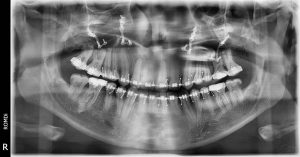

La radiografía panorámica permite la observación de ambos maxilares y la dentición, presentando una serie de relaciones únicas entre estas estructuras que no pueden ser encontradas en otro tipo de radiografías.